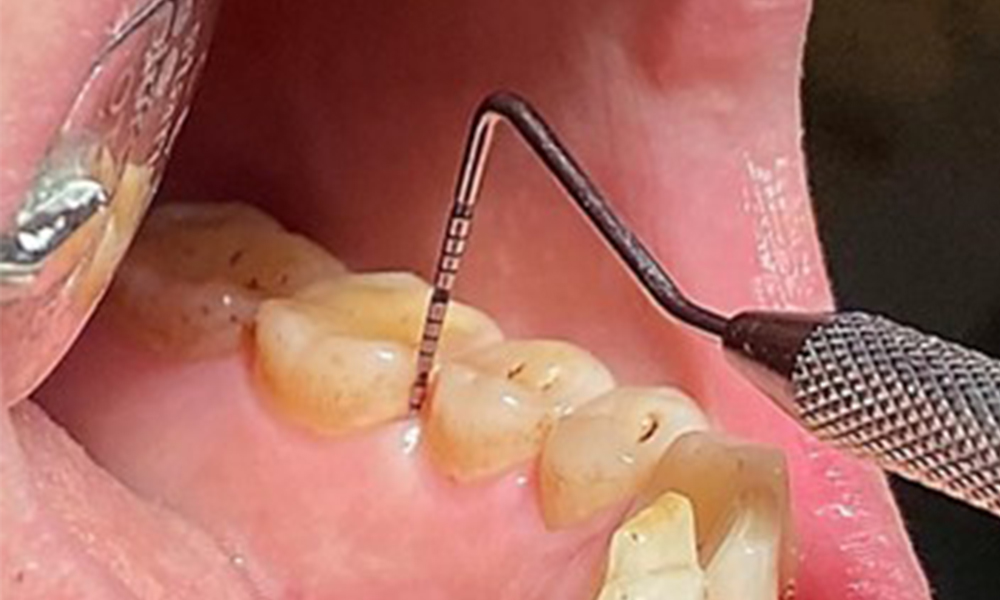

Пародонтални резултати

Клиничните дълбочини на сондиране от 1 до 3 мм са във физиологичния диапазон. От 13 до 16 и от 23 до 27 се наблюдават максиларни рецесии до 1 mm. BOP е 15 %.

Поради иначе благоприятното общо медицинско състояние, нуждите, определени по време на оралния преглед, ще бъдат решаващи за лечението. От съществено значение ще бъде периодичното определяне на дълбочината на сондиране. Гингивалното кървене намалява при пушачите, поради което клиничната диагноза на пародонтита може да се постави само чрез сондиране (фиг. 7). Поставянето на изключителен акцент върху определянето на индексите на кървене може да замъгли съществуващ пародонтит или гингивит. (5)

- Важно е да се документират резултатите от контролния преглед. По време на всяка среща трябва да се определя статусът на кървене при сондиране (BOP) за измерване на дълбочината на пародонталния джоб в ранните етапи на заболяването. Това е особено важно при пушачите поради намален приток на кръв към тъканите.